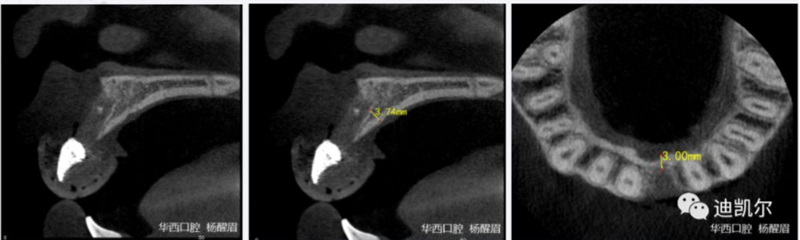

術(shù)前CBCT圖像和測量數(shù)據(jù)

*CBCT顯示骨缺損嚴重,種植窩洞制備困難,種植體很難獲得初期穩(wěn)定性

患者佩戴此U型管開合拍攝CBCT,其中可以獲得缺牙區(qū)修復(fù)體的切端及齦緣等信息

患者佩戴此U型管開合拍攝CBCT,U型管中的放射標記點清晰顯影

設(shè)計軟件中,選擇適合的種植體

根據(jù)修復(fù)體形態(tài),軸向以及骨量將種植體放置最適合的位置